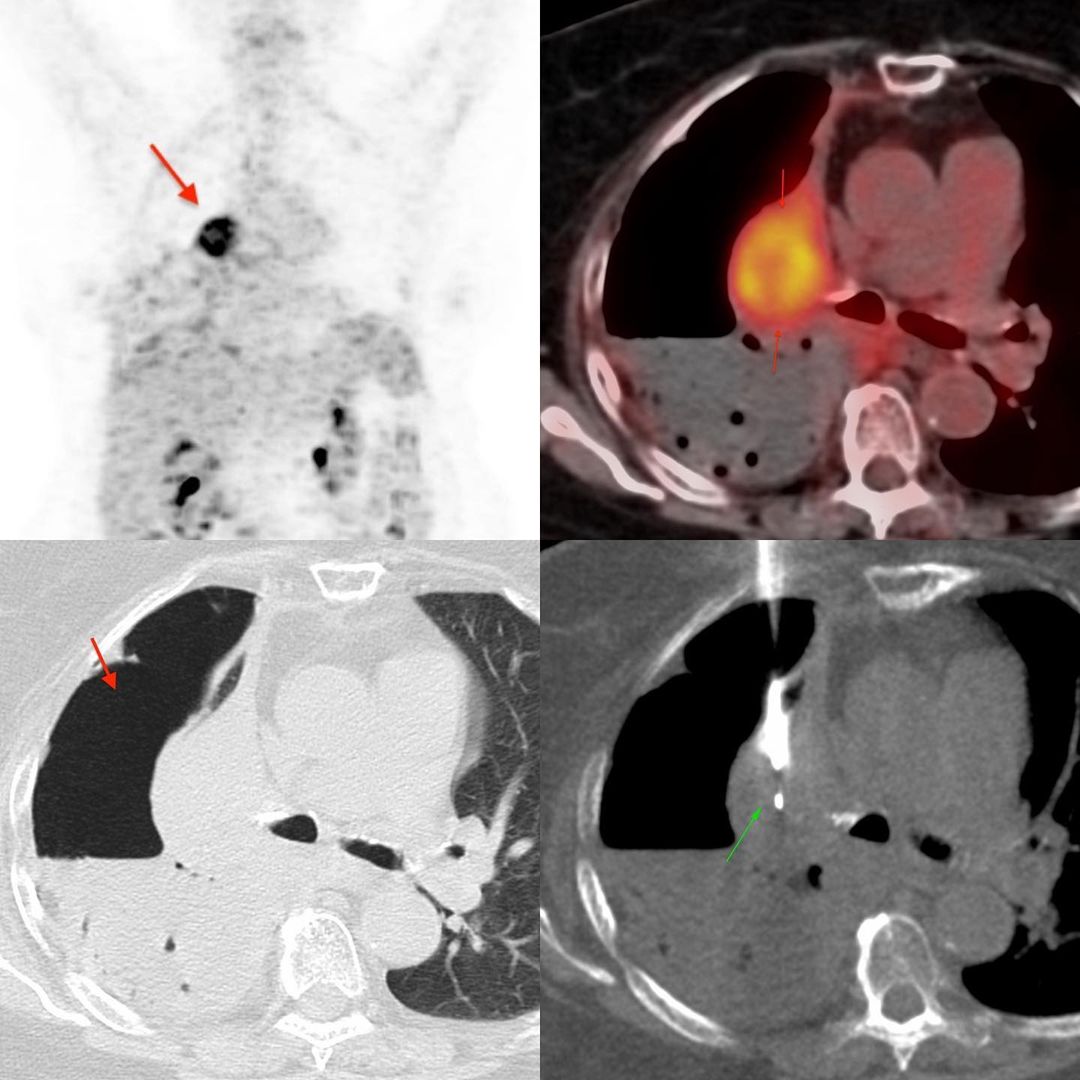

This 81 years old lady presented with a hydropneumothorax. A CT scan showed a possible mass in the atelectatic right upper lobe. A PET/CT confirmed a mass with uptake.